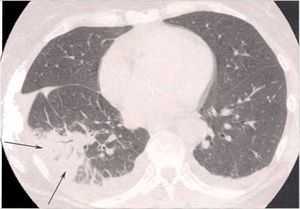

Начальный этап бактериального воспаления легких.

КТ ОГК. Множественные обширные участки снижения пневматизации по типу консолидации в нижних долях обоих легких.